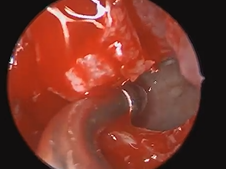

Microdirect Laryngoscopy and CO2 Laser Total Vestibulectomy for Pyolaryngocele

- Date : 01/01/2020

Microdirect Laryngoscopy with CO2 Laser Wedge Excisions for Subglottic Stenosis